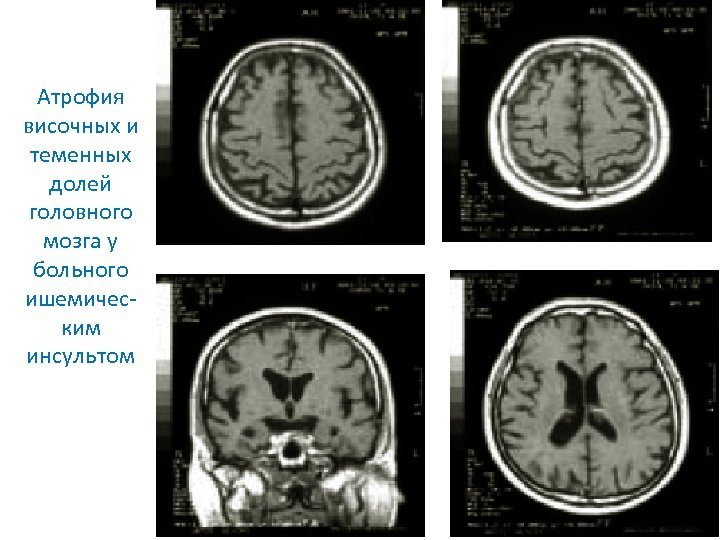

Атрофия височных и теменных долей головного мозга у больного ишемическим инсультом